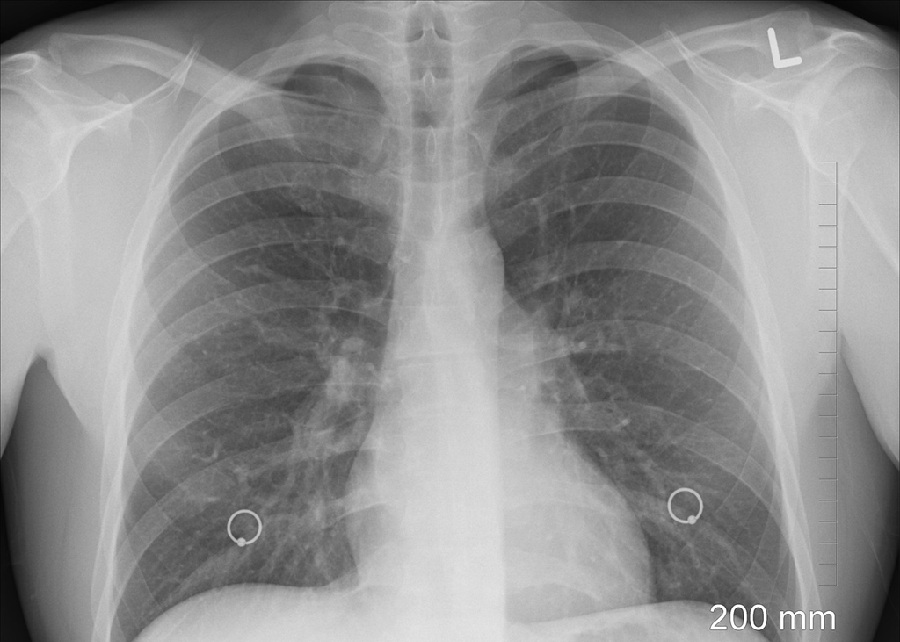

Bolest može zahvatiti različite organe, ali se u najvećem broju slučajeva razvija u plućima. Važno je naglasiti da jedna neliječena osoba može zaraziti veći broj ljudi u svojoj okolini, zbog čega je ključno rano prepoznavanje simptoma i pravodobno liječenje.